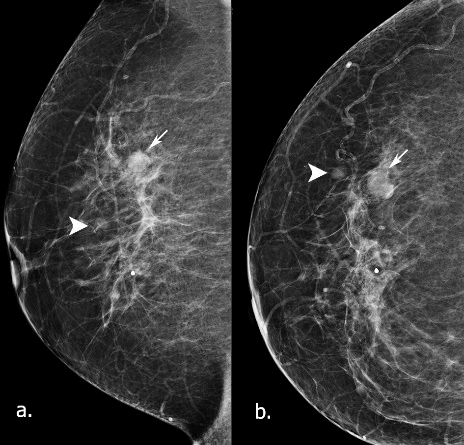

Figure 1: Mammograms in 2015. a) MLO b) CC view. In the upper outer of the right breast, two isodensity, well-defined opacities seen (arrow and arrow head). The lesions were graded as M2 in the UK 5 point grading system (equivalent to BIRADS-3).

During the breast screening program in 2015, a 60-year old Bangladeshi lady was recalled for further investigation, as two relatively well-defined, isodensity opacities were identified in the mammograms of the right breast, measuring 12 mm and 5 mm (Figure 1). In the subsequent US examination (Figure 2), at 10 o’clock, a thin-walled cystic lesion noted measuring 12x8 mm. No internal vascularity was identified with the use of power Doppler. The lesion was graded as U2 in the 5-point UK classification system (equivalent to BIRADS-3) and was aspirated to dryness with the use of a 21-gauge needle [10]. Τhe content was slightly blood-stained and was sent for cytology, which was reported as C2 (normal cystic content). Additionally, 30 mm apart from the cystic lesion, a 5mm well-defined isoechoic nodule was identified, without significant vascularity in the power Doppler. An inspissated cyst and a papillary lesion were in the differential diagnosis and were graded as U3 in the 5-point UK classification system (equivalent to BIRADS-4a) [10]. A 14-gauge needle core biopsy was performed that showed an infarcted papillary lesion, without atypia. Following this, an US-guided vacuum excision with a 10-gauge needle took place and a marker clip was deployed at the side. The patient returned to routine screening.